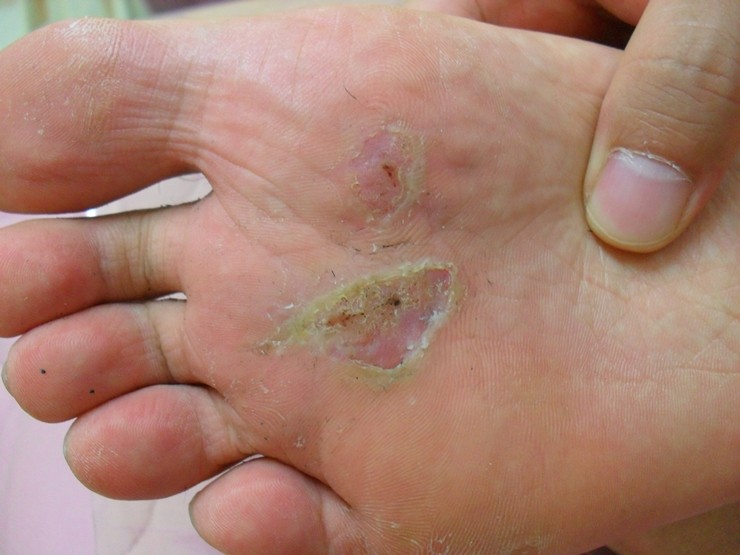

사마귀 치료 사진입니다.

2015-03-11

광주점

질환

피부질환

상세질환

사마귀

더 많은 치료후기 및 전후사진은 광주 후한의원 카페에서 보실 수 있습니다.